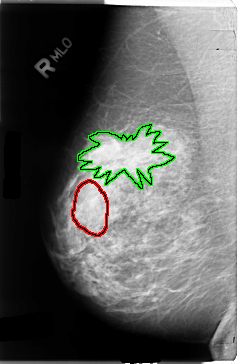

B_3036_1.RIGHT_CC

FILE: B_3036_1.RIGHT_CC.OVERLAY

TOTAL_ABNORMALITIES 2

ABNORMALITY 1

LESION_TYPE MASS SHAPE LOBULATED MARGINS CIRCUMSCRIBED-OBSCURED

ASSESSMENT 3

SUBTLETY 3

PATHOLOGY UNPROVEN

TOTAL_OUTLINES 1

BOUNDARY

ABNORMALITY 2

LESION_TYPE MASS SHAPE ARCHITECTURAL_DISTORTION MARGINS ILL_DEFINED-SPICULATED

ASSESSMENT 4

SUBTLETY 4

PATHOLOGY MALIGNANT